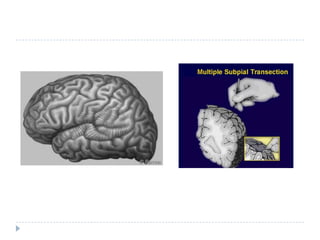

Multiple subpialtransections (MST)MST may be an option for patients with RE whose seizures begin in areas of the brain that cannot be safely removed. In addition, there must be a reasonable chance that the person will benefit from surgery. MST stops the seizure impulses by cutting nerve fibers in the grey matter of the brain sparing the vital functions concentrated in white matter. It is reported to achieve a significant seizure reduction

Multiple subpialtransections (MST)MSTmay be an option for patients with RE whose seizures begin in areas of the brain that cannot be safely removed. In addition, there must be a reasonable chance that the person will benefit from surgery. MST stops the seizure impulses by cutting nerve fibers in the grey matter of the brain sparing the vital functions concentrated in white matter. It is reported to achieve a significant seizure reduction